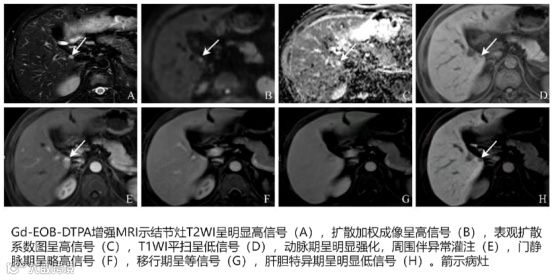

患者男性,36岁、HBV相关性肝硬化,MR示:肝VI段异常信号;脾大。

特点:本例患者动脉期强化,门脉期、平衡期稍高信号,但门脉期无廓清。

结节MRI:T2WI呈稍高信号,扩散加权成像呈高信号,动脉期强化,移行期等信号或稍低信号,肝胆特异期低信号。

HCC:表观扩散系数图(Apparent Diffusion Coefficient,ADC)呈低信号,动脉期强化+门脉期或移行期非边缘廓清(等信号或稍低信号)。

海绵状血管瘤:ADC呈高信号,动脉期强化+门脉期或移行期进一步强化(稍高信号或等信号)。